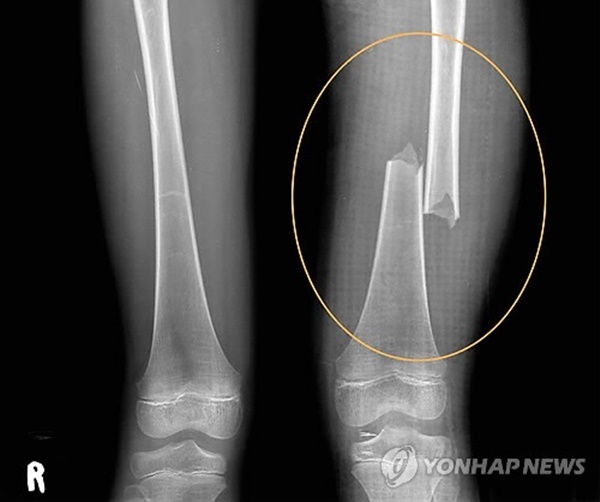

Vào ngày 21/5/2012, Park đã đập vào đùi của bé Lee nhiều lần khiến cho đứa trẻ bị gãy xương, phải mất 10 tuần điều trị mới hồi phục. Nguyên nhân chỉ bởi vì bé Lee về nhà muộn 10 phút nhưng câu chuyện lại bị Park che đậy bằng lời nói dối, rằng đứa trẻ bị ngã xuống cầu thang ở trường.